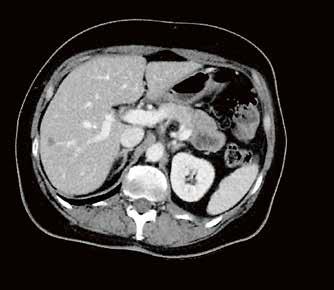

Fall 1:

Biphasische Abdomen-CT bei einer deutlich adipösen Patientin. Hier lässt sich sowohl Dosis sparen als auch die Qualität der Rekonstruktionen verbessern. Beispielsweise findet sich deutlich weniger Bildrauschen, insbesondere im Bereich der parenchymatösen

Fall 2:

Portalvenöse Abdomen-CT. Auch hier ist die Dosis am Aquilion Prime SP mit AiCE geringer, zudem auch hier geringeres Bildrauschen mit sehr guter Abgrenzbarkeit, beispielsweise von Leberläsionen.

Abb. 1 a: biphasische Abdomen-CT, Canon Aquilion Prime, Rekonstruktion: AIDR 3D; DLP 1003,6 mGy × cm / 18,1 mSv. Abb. 2 a: biphasische Abdomen-CT, Canon Aquilion Prime, Rekonstruktion: AIDR 3D; DLP 1003,6 mGy × cm / 18,1 mSv. Abb. 1 b: biphasische Abdomen-CT, Canon Aquilion Prime, Rekonstruktion: AiCE; DLP 716,5 mGy × cm / 12,9 mSv. Abb. 2 b: biphasische Abdomen-CT, Canon Aquilion Prime, Rekonstruktion: AiCE; DLP 716,5 mGy × cm / 12,9 mSv. Oberbauchorgane.